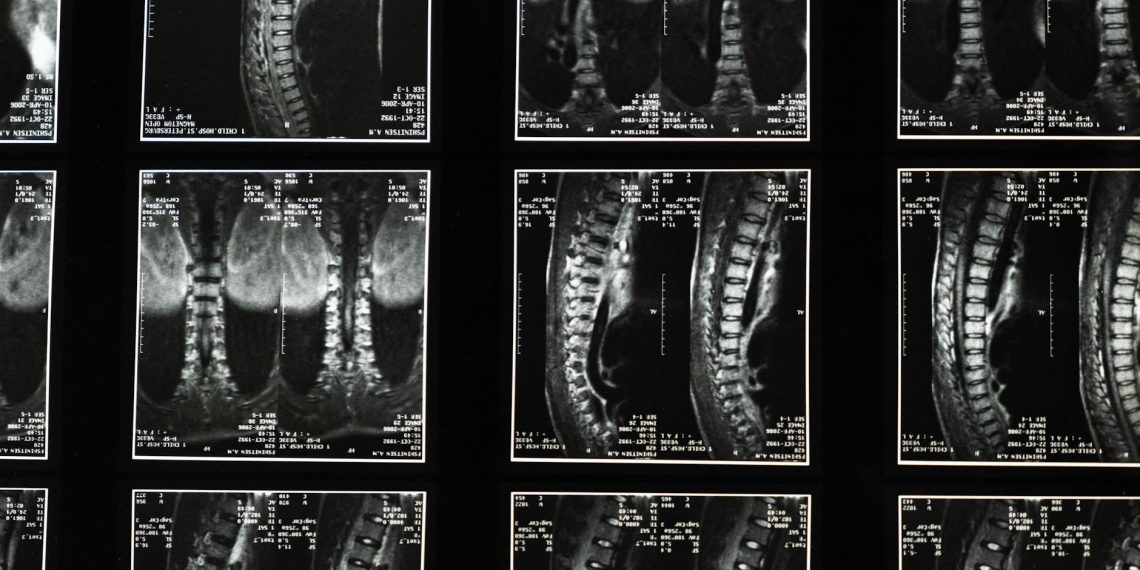

- [Thoát vị đĩa đệm]: Nhân nhầy của đĩa đệm bị lồi ra ngoài và chèn ép lên rễ thần kinh tọa, gây đau.

- Hẹp ống sống: Tình trạng ống sống bị thu hẹp, chèn ép lên dây thần kinh.

- Thoái hóa cột sống: Bao gồm các vấn đề như trượt đốt sống.